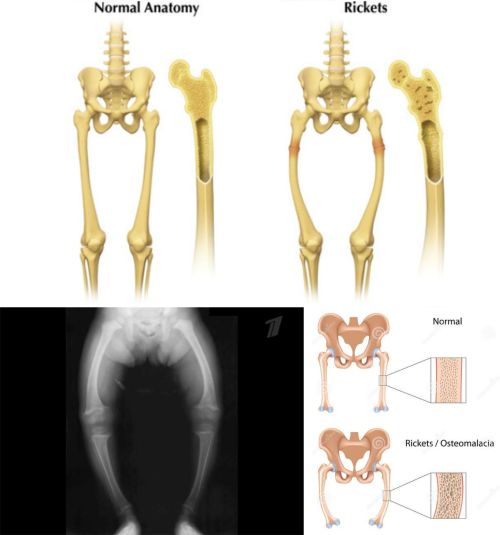

Ad:  r2.gif

Raşitizmin diğer belirtileri ise kemiklerde kalsiyum birikiminin yetersizliğine bağlıdır. Bıngıldak, yaşa göre büyüktür ve kapanması gecikir. El ve ayak bilekleri geniştir. Kaburgaların üzerinde tesbih tanesi gibi şişkinlikler farkedilebilir. Göğüs kafesinin alt kısmında oluk benzeri bir çökme oluşabilir. Diş çıkması gecikir.

Raşitizmli çocukların alınları geniş ve belirgin, karınlari ise şiş gözükür. Eğer hastalık tedavi edilmezse büyüme yavaşlar ve bir süre sonra çocuk boyca yaşıtlarına göre geri kalır. Çocuk yürümeye başladıktan sonraki en önemli bulgu bacaklardaki eğriliktir (O ya da V bacak).

Çoğunlukla klinik bulgular teşhis için yeterli olmakla beraber, kesin teşhis için ya kemik filmi çekilmesi ve/veya kan tahlili ile kalsiyum, fosfor ve alkalen fosfataz düzeylerinin ölçülmesi gerekli olacaktır.